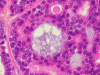

Panel A is a low-magnification photo taken at the edge of the tumor that shows tumor invasion into the surrounding salivary gland tissue. Well formed cribiform arrangment by tumor cells are show in panel B, C, and D; a fibrous stroma can be well appreciated in these photographs. Eosinophilic basement membrane like material can be well recognized in panel E; mucoid material containing microcysts are well illustrated in panel D and F. The myoepithelial component are recognized by strong immunoreactivity for calponin and smooth muscle actin (SMA) in panel G an H; note that the luminal epithelial cells do not have such immunoreactivity. Strong immunoreactivity of the tumor cells for pancytokeratin are well demonstrated in panel I

The histologic features are well illustrated in this case. In general, ADCC is a malignant tumor that is clearly invasive at macroscopic and microscopic levels. Grossly, they are usually fibrous mass with invasion into the surrounding tissue. The stroma of ADCC is typically fibrotic. The common histologic patterns are the cribiform pattern, tubular pattern and solid pattern. The less common pattern are the spindle cell pattern, trabecular pattern and solid type with comedo-type necrosis. Common histologic features are cribriform or microcystic architecture with relatively uniform cells, with small, hyperchromatic nuclei, scant cytoplasm, somewhat nulcear molding and indistinct cytoplasmic border. These cells are considered as myoepithelial differentiation.  A second cell type can be recognized as somewhat larger, with more abundant cytoplasm and less dense nuclear chromatin. These cells are thought to represent ductal epithelial cells. The ductal cells give rise to real tubular structures that contain bluish mucoid material; these cells are immunoreactive for carcinoembryonic antigen (CEA), epithelial membrane antige  (EMA), keratin, and S-100 protein. The myoepithelial cells may arrange in solid sheets and also give rise to microscystic structures containing hyalinized eosinophilic basement membrane-like material. They bear immunoreactivity for calponin, muscle specific actin, and low molecular weight cytokeratin. They are also positive for S-100 protein but are usually less strong than the ductal cells in the same tumor. Many ADCC also express C-kit (CD117) 2, especially in solid type. PAS (+) basement membrane-like material is seen in the pseudocyts and mucin in the true ducts. Perineural invasion is the rule. The tumor cells are highly proliferative and a Ki-67 labeling index over 20% is not uncommon.